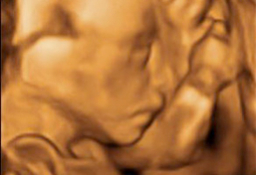

Ecografía de la semana 20 o morfológica, así se denomina esta prueba diagnóstica, considerada como la primera "foto" del bebé. Decimos esto porque el ecografista recorre con mucha calma y cautela todas las estructuras básicas y órganos del bebé, que a esta edad gestacional se suelen ver con claridad. El pequeño aún se mueve con soltura dentro del líquido amniótico, a veces esquivando la mirada del ecografista, algo que en pocas semanas hará con mucha más dificultad. Merece la pena ver esta galería de ecografías de la semana 20 (y alrededores, puesto que se puede hacer a partir de las semana 18) en 2D, 3D y 4D. En la eco de la semana 20 también pueden detectarse algunas malformaciones fetales, pero lo usual que que se compruebe la buena salud del feto.